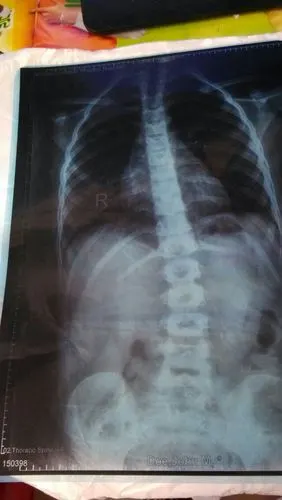

女儿8岁,在医院照x光片,发现胸腰段脊椎略侧突畸形,严重吗?

孩子10岁之前发现脊柱侧弯该如何治疗